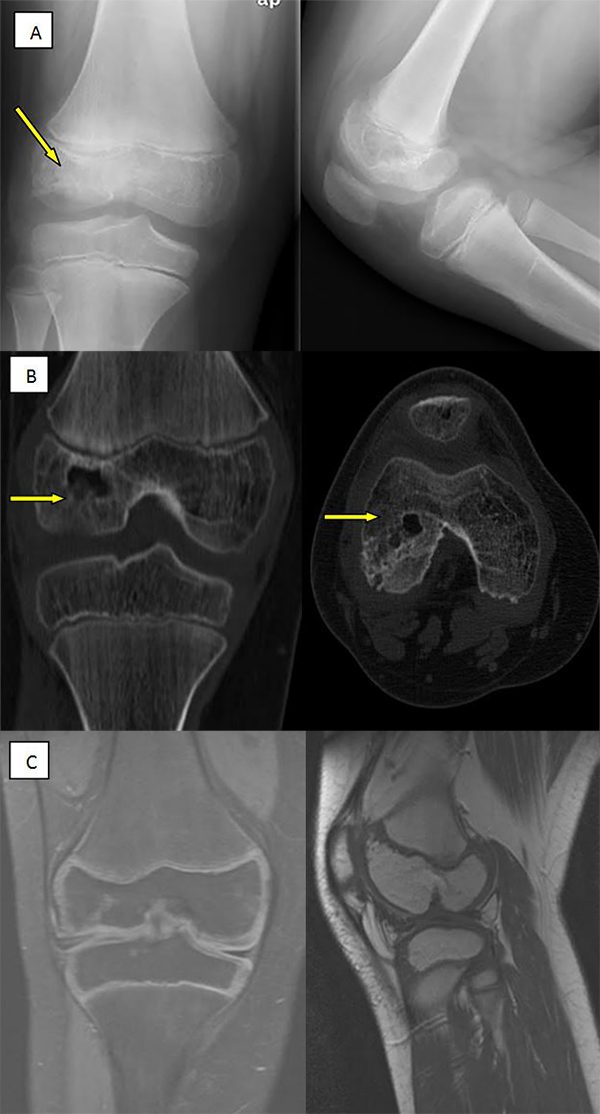

Después de 8 años de seguimiento, el paciente se encuentra asintomático, realizando vida normal, incluso deportiva. En la exploración física destaca como secuelas: dismetría del miembro inferior lesionado con 12 mm más largo y pérdida de últimos grados flexión, sin repercusión funcional (fig. 3). Las imágenes de control evolutivo del TAC y RNM demuestran una mejoría de los defectos óseo y cartilaginoso en cóndilo femoral externo (figs. 4 y 5).

Figura 4: Control evolutivo por imágenes a los 4 años de seguimiento. A) Radiografía frente a la izquierda y perfil a la derecha con aplanamiento de la lesión en cóndilo femoral externo (detalle de la flecha). B) Imagen coronal de TAC a la izquierda y axial a la derecha con disminución del tamaño del defecto óseo. C) Imagen RNM coronal a la izquierda y sagital, apreciándose cambios en cóndilo femoral externo con aplanamiento y remodelado. A pesar de todo persiste defecto condral.